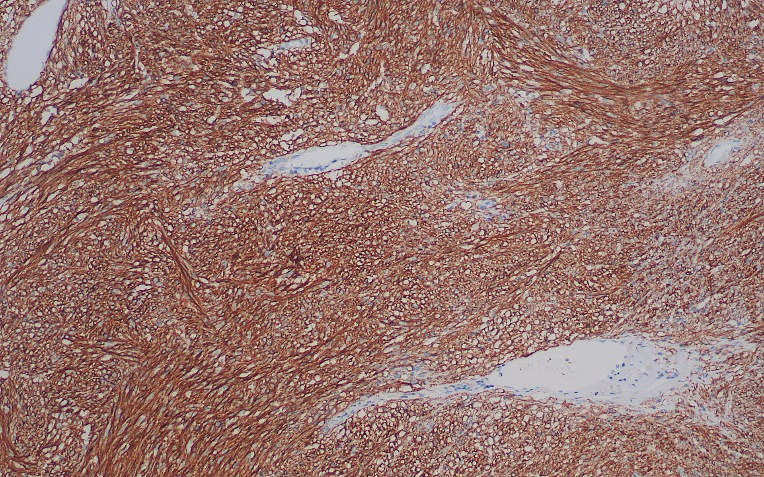

• DOG1胃肠道间质瘤

DOG1基因位于染色体11q13,是一种钙离子调节相关的氯离子通道蛋白。在胃肠道间质瘤(GIST)中显示出高特异性及敏感性。在c-Kit为阴性的GIST中(4-15%),绝大部分存在Dog1的表达,常与CD117联合使用。